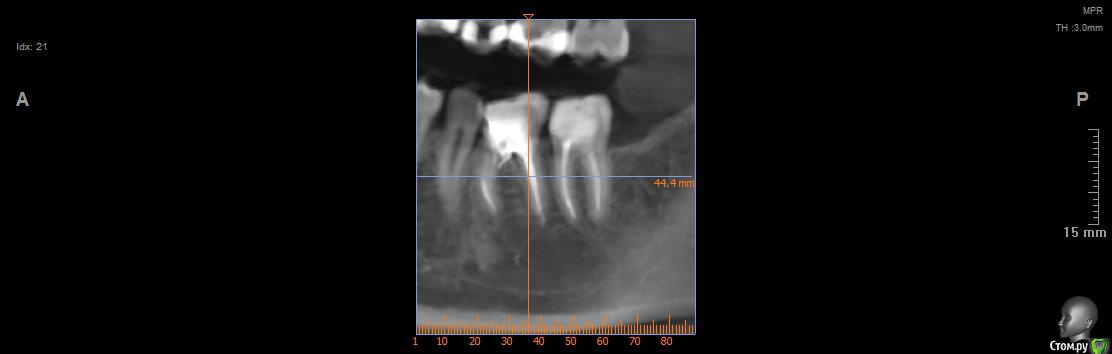

Vords Опубликовано 11 июня, 2020 Поделиться Опубликовано 11 июня, 2020 (изменено) Доброго вечера, профессионалы. Прошу у Вас помощи. Буду очень благодарен за консультацию. 3 недели назад появились боли в в жевательных зубах (около 37 и 36 зубов). В виду того, что боли были достаточно серьезные, а врач, у которого я лечился ранее не мог меня принять из-за пандемии - пришлось идти в городскую поликлинику. По результатам похода был поставлен диагноз пульпит 37 и глубокий кариес 36. На 36 поставили пломбу - 37 успешно депульпировали. На этом история 37 зуба закончена. С 36 после постановки пломбы начались дикие ночные боли и боли при накусывании. На повторном приеме был поставлен диагноз пульпит 36 - поставлено лекарство для умертвления нерва. После этого боль при накусывании прошли. В следующий прием пришел на чистку каналов и пломбировку. Во время этой процедуры я вдруг ощутил совершенно дикую боль (как выяснилось потом - в этот момент и произошла перфорации в области фуркации). Врач ничего не сказал - просто поставил метапекс и запломбировал каналы. В этот момент начались боли при накусывании. а потом постоянная тянущая боль. Продолжалось это около 3 дней - я пошел в другую стоматологию где мне сделали рентген и с подозрение на перфорацию отправили на КТ. По результатам КТ перфорация была подтверждена. С КТ я пришел в городскую стомотологию где мне предложили закрыть перфорацию цементом (pro что-то там - не могу сказать точно). Закрыли ее во вторник на этой неделе. Сегодня восстановили коронку и поставили световую пломбу. Беда в том, что боль при накусывании и "нытье" с этой стороны так и не прошли. По словам стомотолага гос клиники - боль при накусывании из-за метапекса и когда он рассосется - боль пройдет. (до 6 месяцев). Я прилагаю рентген (ужасное качество), фото КТ и ссылку в облако на КТ. Я допускаю, что никто не захочет лезть в облако и тратить свое время на просмотр на КТ (сам не могу разобраться с программой, что бы сделать достойные скрины), но если вдруг у кого-то найдется время - буду очень благодарен. Рентген сделан сразу после пломбировки канала. КТ через 3 дня после этого. В связи с этим вопрос. Возможно ли, что боль при надавливании пройдет если подождать пока рассосется метапекс или это пустая трата времени? Мне стоит ждать какое - то время или в этой ситуации мне поможет только удаление? Благодарю Вас за уделенное время Ссылка на КТ https://cloud.mail.ru/public/44WE/2JeTfXmr2 Изменено 11 июня, 2020 пользователем Vords Ссылка на комментарий

krokomot Опубликовано 11 июня, 2020 Поделиться Опубликовано 11 июня, 2020 Судя по всему у вас в 6м зубе выведен не только метапекс но и гуттаперчевый штифт, скорее всего, если это не исправить боли сохранятся, и что там с коронкой не понятно, на кт сильные тени из-за большого объема рентгеноконтрасного материалла, а прицельный снимок что вы сделали, сделан не поп правилам и на нем сильные искажения, понять трудно что с коронкой. Короче, зуб с перфорацией , выведенным материалом за апексом и гуттаперчей, и при этом еще и беспокоит, прогноз сомнительный. возможно всё можно переделать и всё станет нормально , но это не точно. Вам нужен грамотный доктор эндодонтист. 1 Ссылка на комментарий

wladdX Опубликовано 11 июня, 2020 Поделиться Опубликовано 11 июня, 2020 (изменено) Скриншоты Изменено 11 июня, 2020 пользователем wladdX 1 Ссылка на комментарий

Vords Опубликовано 11 июня, 2020 Автор Поделиться Опубликовано 11 июня, 2020 (изменено) WladdX, огромное спасибо Вам за потраченное на скрины время. А то я так и не смог освоить эту программу (рукалицо). У меня даже есть ощущение, что я вижу теперь штифт, о котором говорил krokomot (хотя и не факт)))) Изменено 11 июня, 2020 пользователем Vords Ссылка на комментарий

krokomot Опубликовано 12 июня, 2020 Поделиться Опубликовано 12 июня, 2020 Да есть 2 Ссылка на комментарий